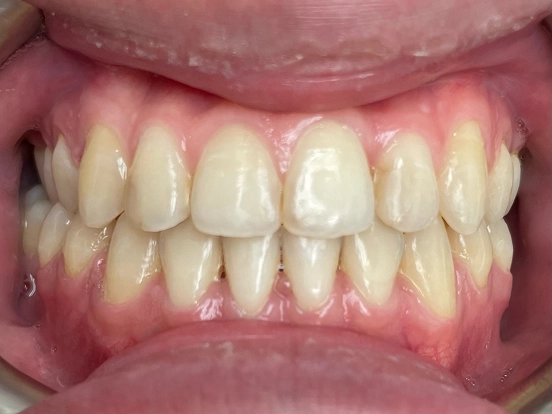

Invisalign DT

DT’s transformation with Invisalign is a perfect example of how advanced orthodontic technology can deliver incredible results. The clear aligners gradually corrected the alignment and bite issues, creating a straighter, healthier, and more attractive smile—all without noticeable brackets or wires.